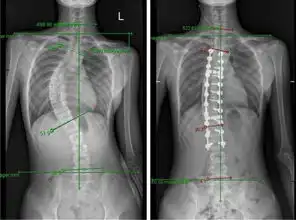

宁海14岁女孩脊柱侧弯达32度,已发病好几年可半个月前学校的体检报告却显示正常